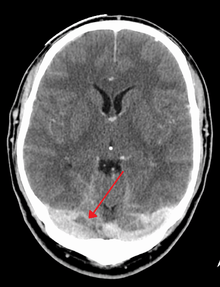

A dural venous sinus thrombosis of the transverse sinus. Greater on the right than left.

There are various neuroimaging investigations that may detect cerebral sinus thrombosis. Cerebral edema and venous infarction may be apparent on any modality, but for the detection of the thrombus itself, the most commonly used tests are computed tomography (CT) and magnetic resonance imaging (MRI), both using various types of radiocontrast to perform a venogram and visualise the veins around the brain.[1]

Magnetic resonance venography employs the same principles, but uses MRI as a scanning modality. MRI has the advantage of being better at detecting damage to the brain itself as a result of the increased pressure on the obstructed veins, but it is not readily available in many hospitals and the interpretation may be difficult.[5]